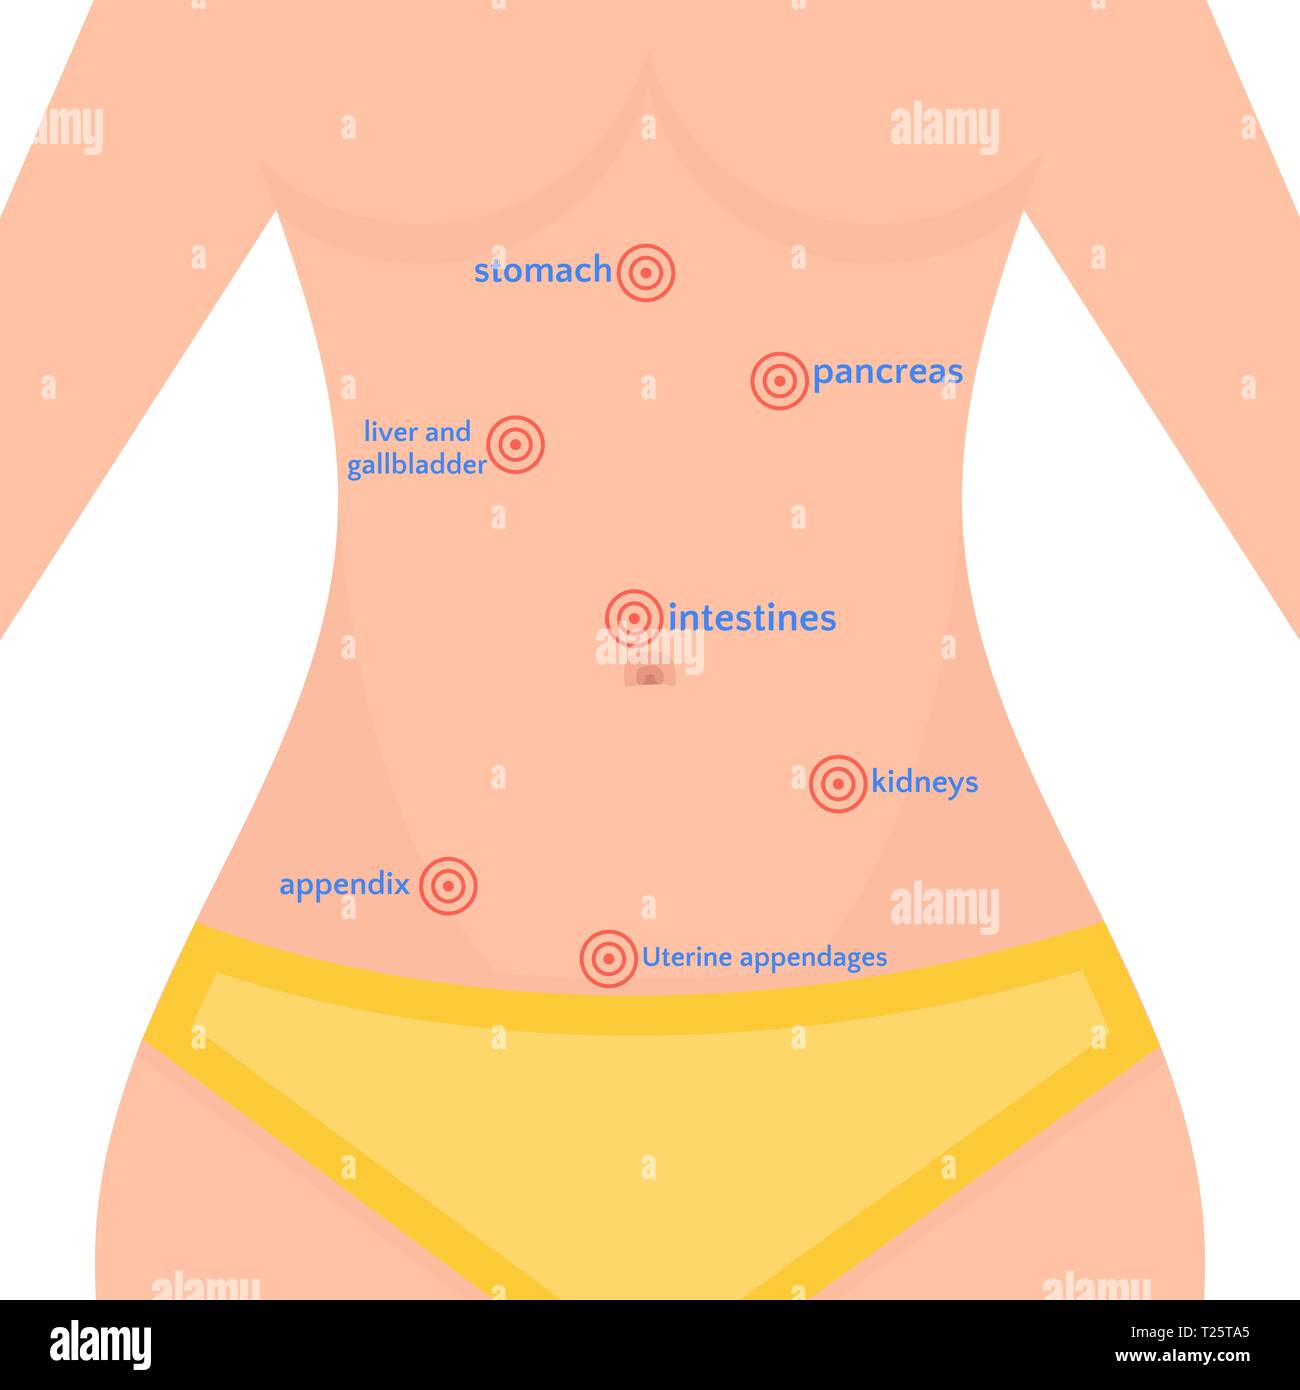

Female Abdominal Pain | Types | Symptoms | Causes | Diagnosis | Treatment

What Is Pain In Lower Right Side Of Stomach – StomachGuide.net